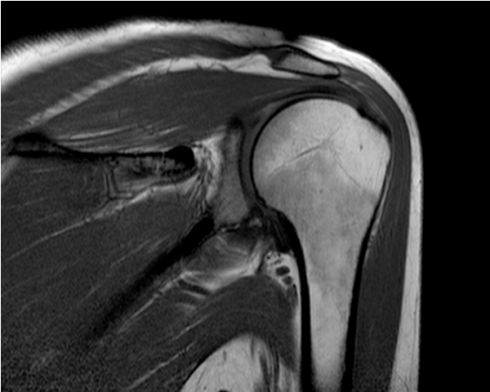

RISONANZA MAGNETICA (ALTO CAMPO) 1,5T

• Rm Spalla anche Con Mdc